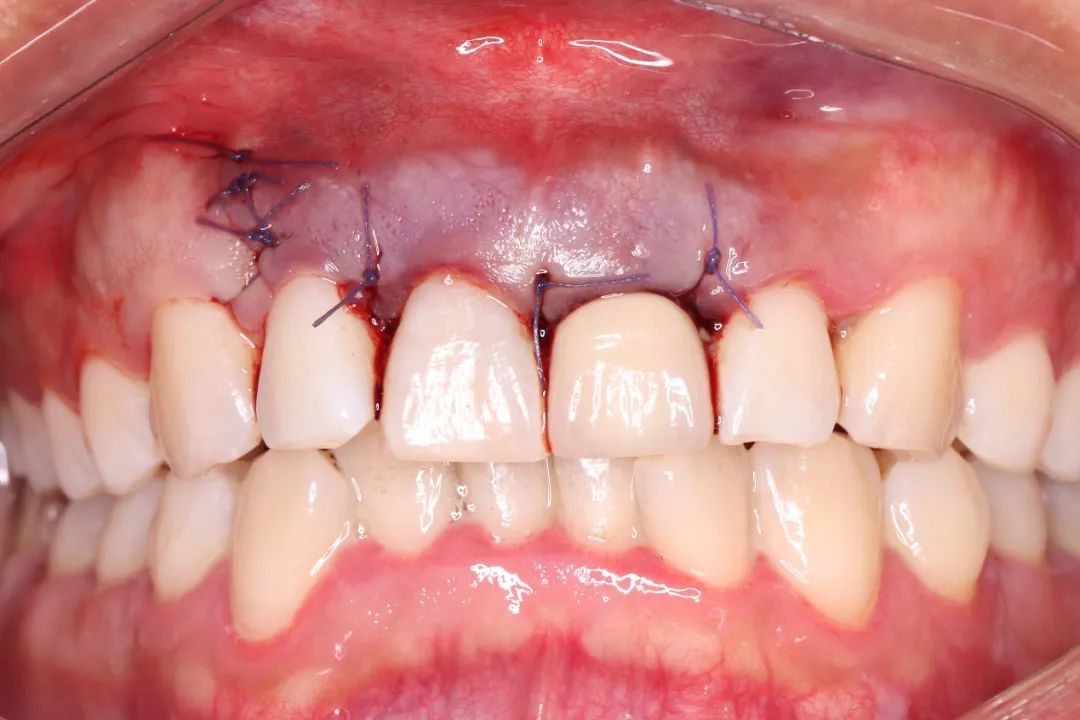

术后即刻照片